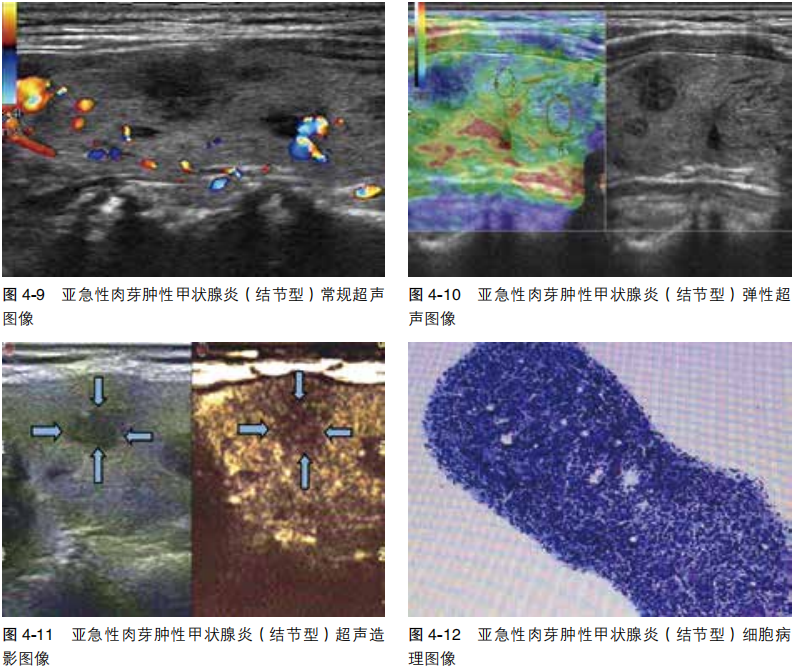

亚急性肉芽肿性甲状腺炎(结节型)

image.png

图像与特征

常规超声 左叶实性结节,低回声,边缘毛刺,纵横比>1,无包膜,边界不清,边缘血流分布不规则。

弹性超声 弹性评分4级。

超声造影 结节呈不均匀低增强,增强范围略大于二维范围,边界尚清,慢进快退。

分析与诊断

常规超声 实性结节(2分),低回声(2分),纵横比>1(3分),边缘不规则(2分),ACR TI-RADS 5类(9分),可疑恶性结节,建议FNAC确诊。

弹性超声 符合恶性结节。

超声造影 可疑恶性结节。

细胞病理 左叶亚急性肉芽肿性甲状腺炎,BRAF V600E基因未见突变。

本例3种超声评估均提示恶性可能,FNAC是可靠确诊方法。

病例2

常规超声 左叶实性结节,低回声,边缘多发毛刺,纵横比>1,无包膜,边界尚清。

超声造影 结节向心性增强,由外向内逐渐降低,边缘模糊,范围略大于二维。

常规超声 实性结节(2分),低回声(2分),边缘不规则(2分),纵横比>1(3分),ACR TI-RADS 5类(9分),可疑恶性结节,建议FNAC。

超声造影 不符合良性结节表现,不排除肉芽肿性结节。